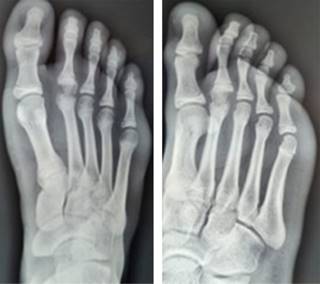

Caso clínico 2. Masculino de 15 años, sufre contusión directa en dorso del pie derecho al jugar fútbol, posteriormente inicia con dolor y marcha antiálgica, motivo por el cual acude a valoración. A la exploración física llama la atención el acortamiento del segundo dedo, con aumento de volumen y edema en dorso de articulación metatarsofalángica del segundo dedo. Se toman radiografías AP y oblicua de pie (Figura 4); evidencian fractura epifisiaria desplazada de la cabeza del segundo metatarsiano.

Figura 4: Radiografías anteroposterior y oblicua del pie de masculino de 15 años. Muestra fractura desplazada de la epífisis del segundo metatarsiano.

Con previo consentimiento de los padres y el paciente, se realiza reducción cerrada bajo anestesia local, se comprueba adecuada reducción con control radiológico (Figura 5). Se coloca zapato postquirúrgico y se inicia marcha a tolerancia. En seguimiento a corto, mediano y largo plazo sin evidencia de complicaciones; se anexan radiografías (Figura 6) a 30 meses de evolución.

Figura 5: Radiografías anteroposterior y oblicua del pie posteriores a reducción cerrada de la fractura. Se observa restitución de la anatomía y longitud.